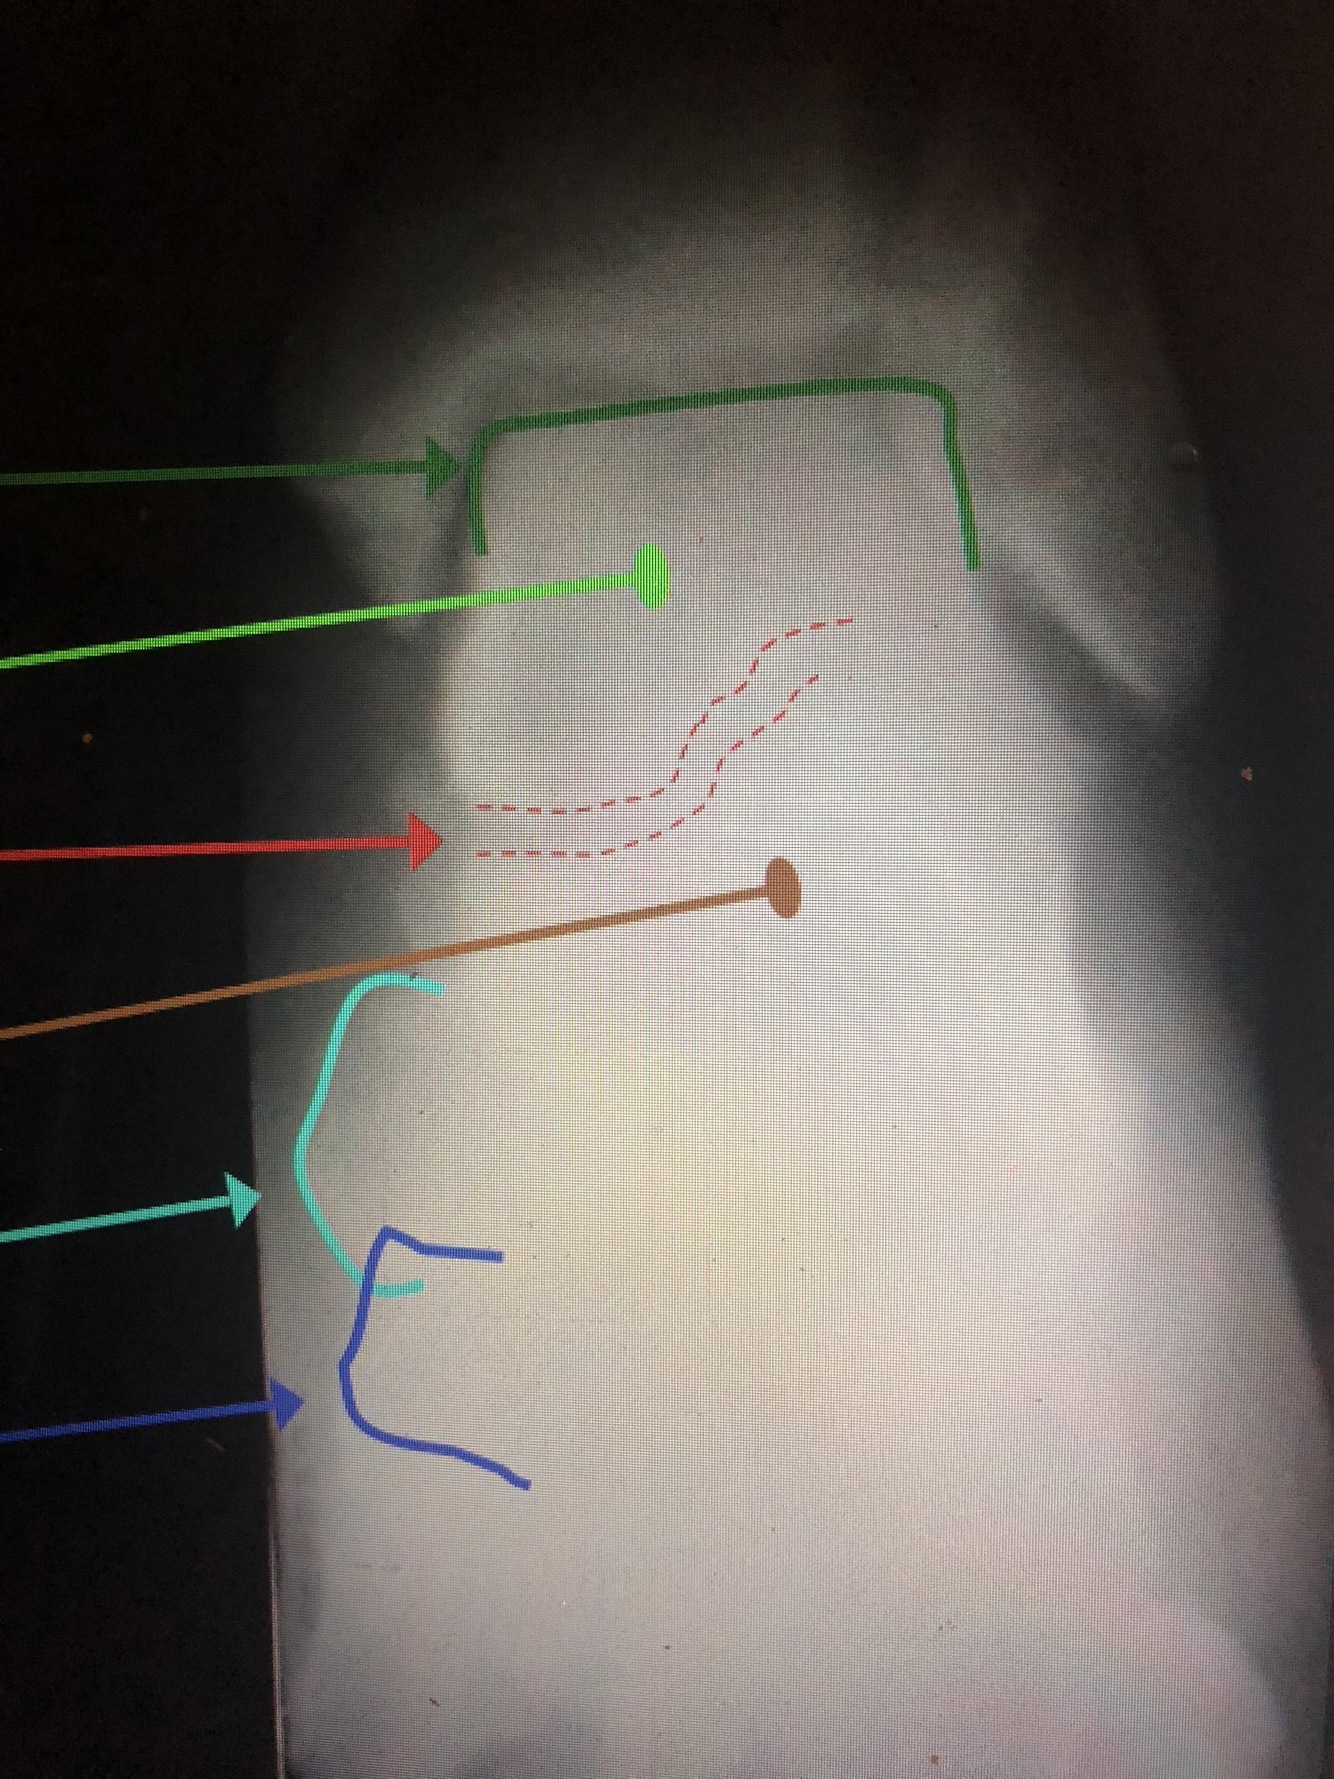

What is the green?

distal Fibular Shaft

What is the red?

Lateral Malleolus

What is the light blue dotted line?

Malleolar Fossa

What is the dark green line?

Talar Dome (Trochlea)

Which bone is the light green?

Talus

What is between the red dotted lines?

Talocalcaneal (Subtalar) Joint

What bone is the brown?

Calcaneus

What is the light blue line?

Navicular Tuberosity

What is the dark blue line?

Medial Cuneiform